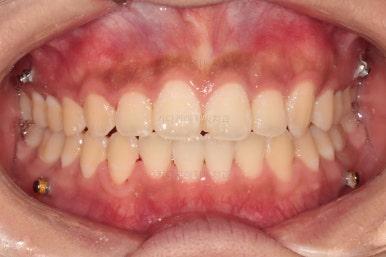

부산치아교정치과 초진 시 입안의 모습입니다.

앞니쪽이 위아래 모두 삐뚠 상태였고요.

왼쪽은 덧니로 툭 튀어나가 있고, 상대적으로 작은 앞니는 안으로 말려 들어가 아랫니와도 거꾸로 물리는 상태였습니다.